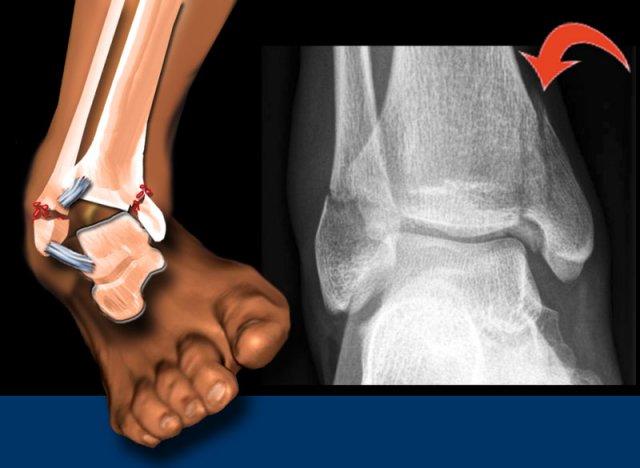

Stage 4

Cuối cùng dây chằng chày mác sau bị đứt, hoặc có sự bong gân của mắt cá sau, còn được gọi là gãy mắt cá sau (mũi tên đỏ).

Khoang sáng phía trong chỉ giãn rộng nhẹ, nhưng dựa trên các giai đoạn của Lauge Hansen, chắc chắn phải có đứt dây chằng bên.

Phim X-quang cho thấy gãy xương Weber C.

Có gãy xương giật (avulsion) của mắt cá trong và gãy xương mác ở trên mức khớp chày mác xa (syndesmosis).

Theo phân loại Lauge-Hansen, đây là tổn thương xoay ngoài-sấp (pronation exorotation) giai đoạn 3, do đó dây chằng chày mác xa trước (anterior syndesmosis) (giai đoạn 2) cũng phải bị đứt.

Chúng tôi không thấy gãy xương tertius, vốn là dấu hiệu của giai đoạn 4, nhưng có thể có rách khớp chày mác sau.

Đây là một ví dụ về gãy xương Weber C kèm theo gãy xương mác đoạn gần.

Lưu ý rằng trên phim X-quang cổ chân không thấy đường gãy xương.

Bạn có thể chẩn đoán nhầm đây chỉ là sưng nề phần mềm đơn thuần.

Thực tế đây là gãy xương cổ chân không vững, vì chắc chắn phải có kèm theo đứt dây chằng bên trong (giai đoạn 1), do đó vòng xương bị phá vỡ ở hai vị trí dẫn đến mất vững.